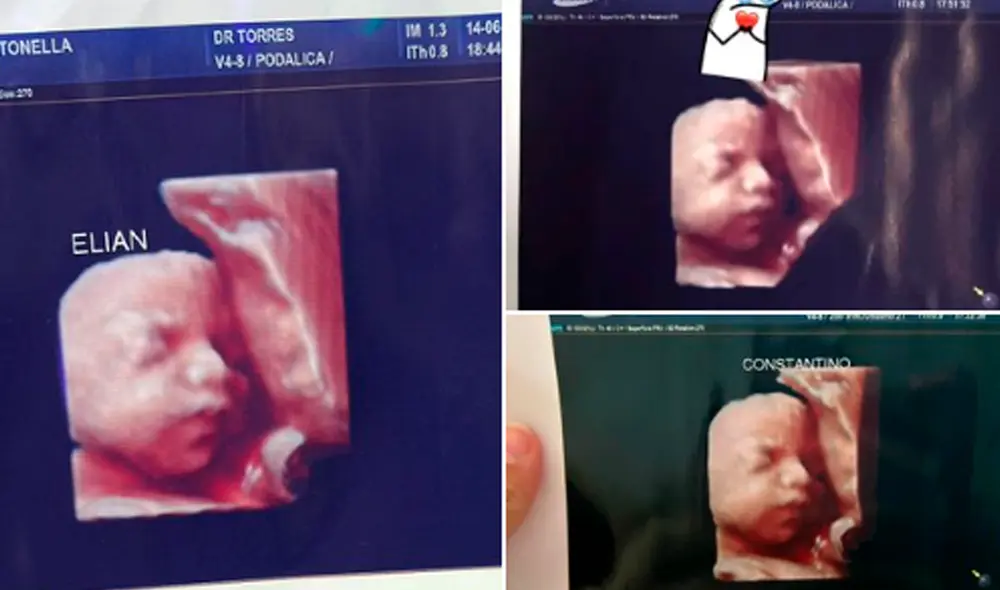

En la ciudad de Formosa, Argentina, al menos cinco mujeres gestantes denunciaron haber sido estafadas por una clínica donde se realizaron supuestas ecografías 5D para ver el rostro de sus bebés antes del parto. El engaño fue descubierto luego de que una de ellas publicara en redes sociales la ecografía que le entregaron en el centro médico; sin embargo, grande fue su sorpresa al recibir mensajes de otras personas embarazadas que aseguraban tener las mismas imágenes.

“Nos estafaron”, coinciden las afectadas, quienes evalúan cómo demandar al establecimiento. El hecho trascendió en medios locales, ya que varias mujeres denunciaron que la clínica privada E. D. de Formosa, realizaba ecografías 5D y les entregaba las mismas imágenes a todas las clientas.

Cuando la estafa salió a la luz, luego del posteo de una de las víctimas, quien mostraba orgullosa la primera captura del rostro de su bebé, empezaron comentarios como: "Ese no puede ser tu bebé" o "Tengo la misma imagen".

“Por ahora somos tres mamás a las que una clínica estafó con una foto de un bebé que no es el nuestro”, denunció Antonella Roglan por medio de Twitter, en la que también adjuntó las ecografías falsas y remarcó que el examen "es carísimo". Pocas horas después, añadió: "ya somos cuatro las estafadas".